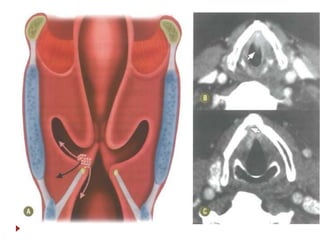

 Do osso hioide ao esôfago cervical.

 Três áreas de interesse:

 Seio piriforme (65%).

 Região pós-cricoide

 Parede posterior

 Os linfáticos drenam para cadeia

jugular e cruzam para o lado

contralateral (II, III, V e

retrofaríngeos).

 Sintomas: disfagia, rouquidão,

dispneia.

 Patologia: CEC.

Hipofaringe  Do ossohioide ao esôfago cervical.  Três áreas de interesse:  Seio piriforme (65%).  Região pós-cricoide  Parede posterior  Os linfáticos drenam para cadeia jugular e cruzam para o lado contralateral (II, III, V e retrofaríngeos).  Sintomas: disfagia, rouquidão, dispneia.  Patologia: CEC.